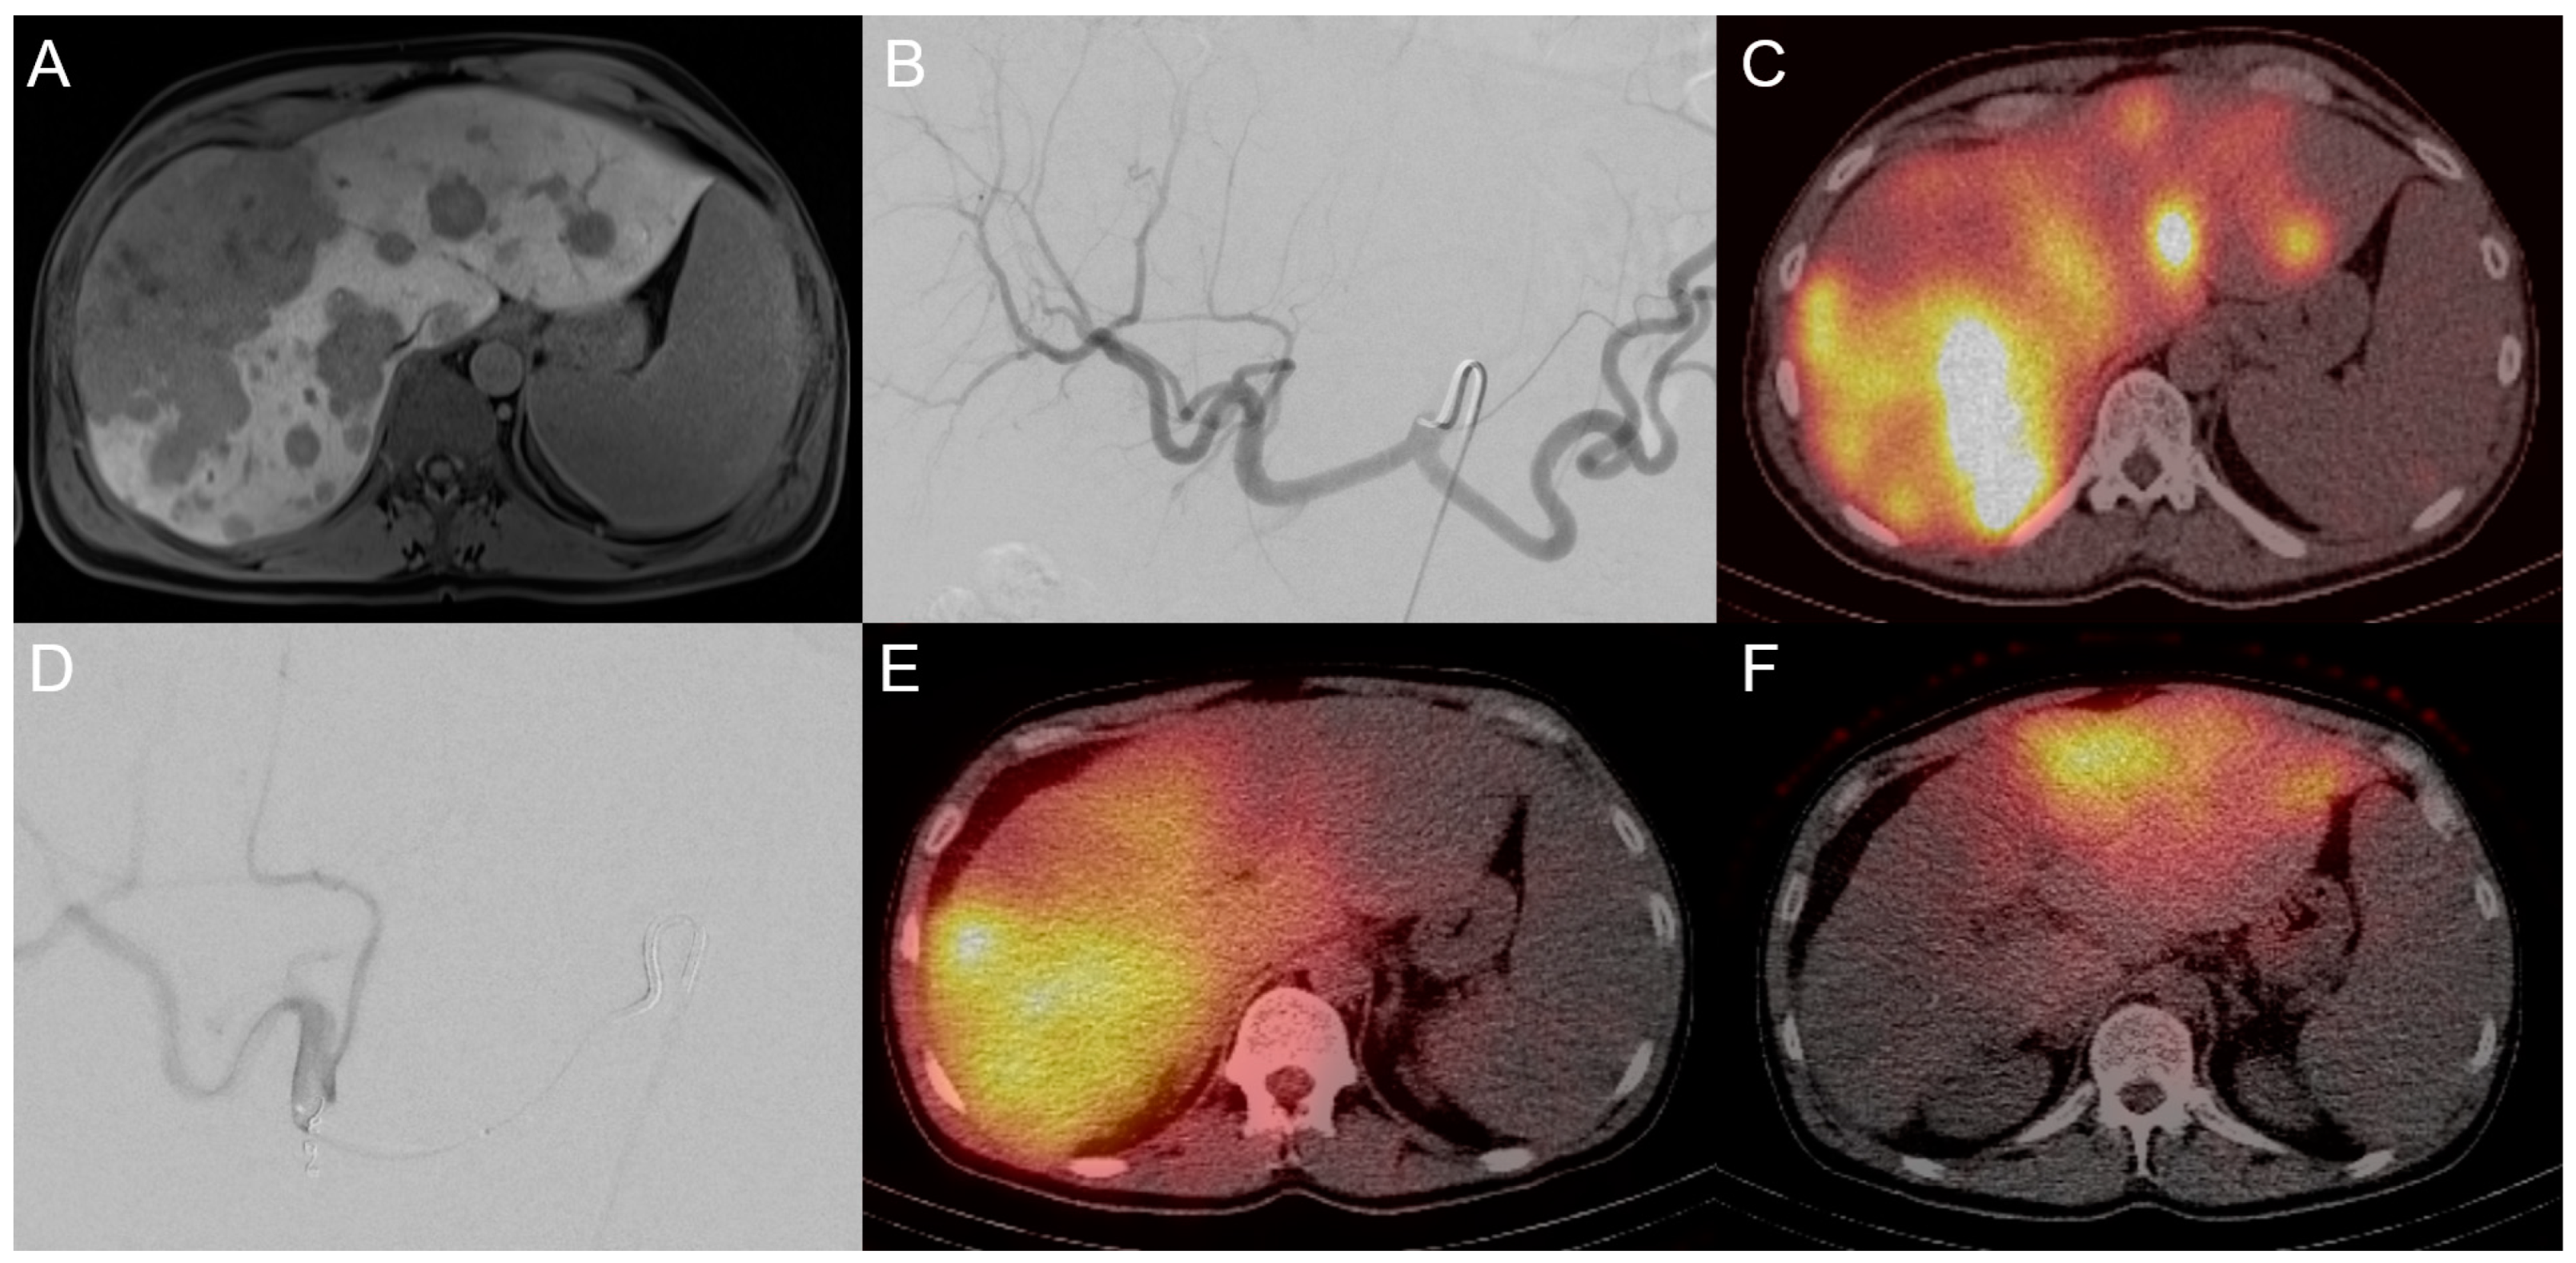

3.2. Transarterial Radioembolization (TARE)

- Gangi, A.; Shah, J.; Hatfield, N.; Smith, J.; Sweeney, J.; Choi, J.; El-Haddad, G.; Biebel, B.; Parikh, N.; Arslan, B.; et al. Intrahepatic Cholangiocarcinoma Treated with Transarterial Yttrium-90 Glass Microsphere Radioembolization: Results of a Single Institution Retrospective Study. J. Vasc. Interv. Radiol. 2018, 29, 1101–1108. [Google Scholar] [CrossRef]

- Hoffmann, R.T.; Paprottka, P.M.; Schon, A.; Bamberg, F.; Haug, A.; Durr, E.M.; Rauch, B.; Trumm, C.T.; Jakobs, T.F.; Helmberger, T.K.; et al. Transarterial hepatic yttrium-90 radioembolization in patients with unresectable intrahepatic cholangiocarcinoma: Factors associated with prolonged survival. Cardiovasc. Intervent Radiol. 2012, 35, 105–116. [Google Scholar] [CrossRef]

- Buettner, S.; Braat, A.; Margonis, G.A.; Brown, D.B.; Taylor, K.B.; Borgmann, A.J.; Kappadath, S.C.; Mahvash, A.; JNM, I.J.; Weiss, M.J.; et al. Yttrium-90 Radioembolization in Intrahepatic Cholangiocarcinoma: A Multicenter Retrospective Analysis. J. Vasc. Interv. Radiol. 2020, 31, 1035–1043. [Google Scholar] [CrossRef]

- Schaarschmidt, B.M.; Kloeckner, R.; Dertnig, T.; Demircioglu, A.; Muller, L.; Auer, T.A.; Pinto Dos Santos, D.; Steinle, V.; Miederer, M.; Gebauer, B.; et al. Real-life experience in the treatment of intrahepatic cholangiocarcinoma by (90)Y radioembolization: A multicenter retrospective study. J. Nucl. Med. 2023, 64, 529–535. [Google Scholar] [CrossRef] [PubMed]

- Schartz, D.A.; Porter, M.; Schartz, E.; Kallas, J.; Gupta, A.; Butani, D.; Cantos, A. Transarterial Yttrium-90 Radioembolization for Unresectable Intrahepatic Cholangiocarcinoma: A Systematic Review and Meta-Analysis. J. Vasc. Interv. Radiol. 2022, 33, 679–686. [Google Scholar] [CrossRef] [PubMed]